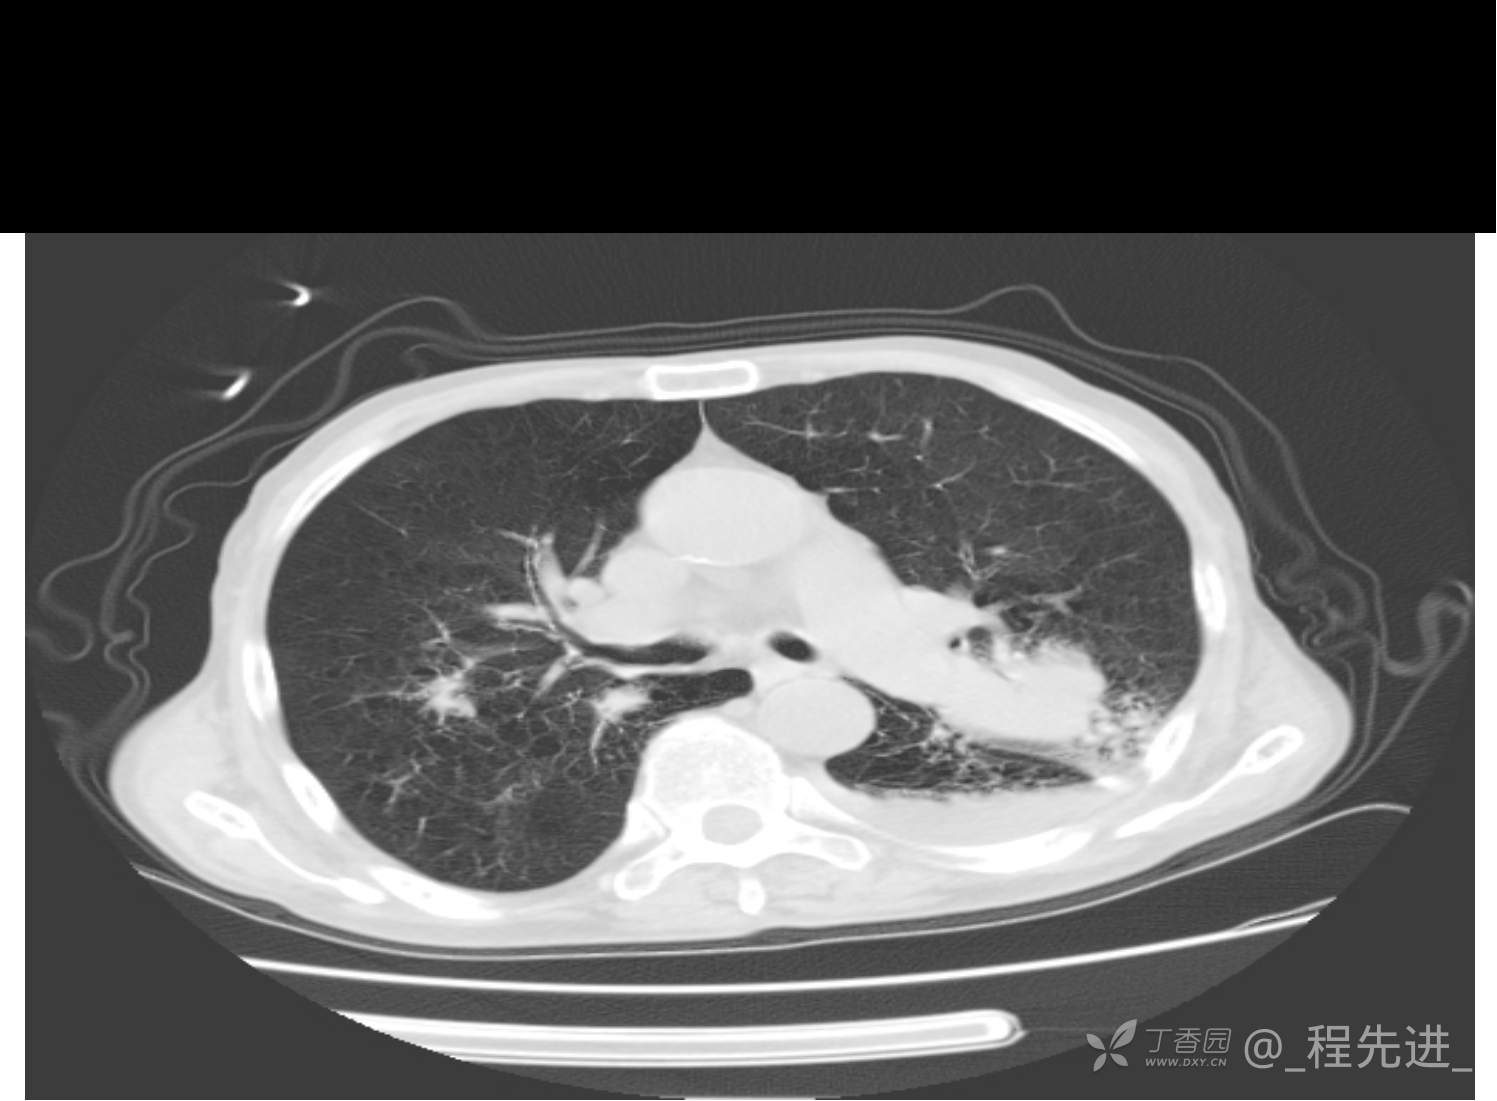

患者性别:男

患者年龄:81岁

简要病史:反复咳嗽、咳痰20余年,加重1周。两肺呼吸音低,可闻及散在干湿啰音。